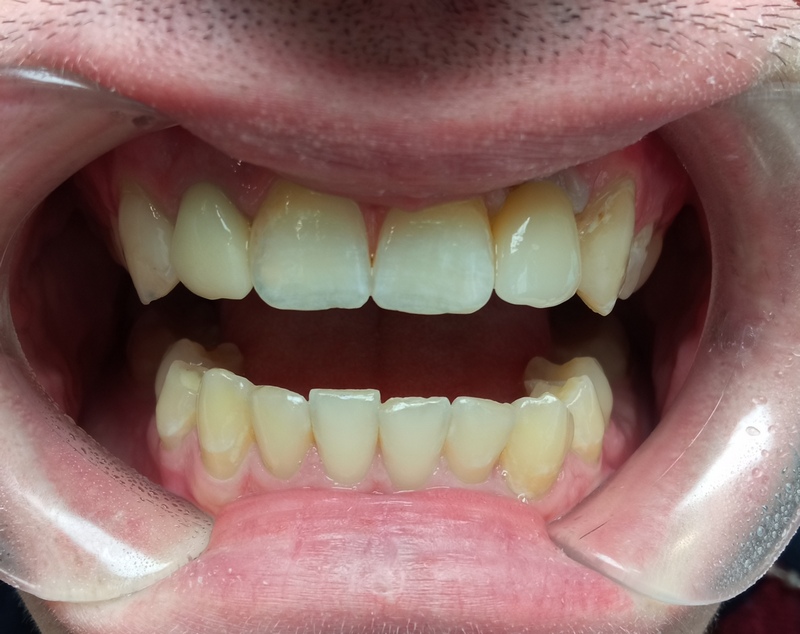

Пример 2

- Провели 3Д КТ обследование 2500 ₽.

- В ходе осмотра состояние полости рта было хорошее, зубы рядом с отсутствующим были сохранены и не поражены кариесом.

- Пациента очень волновало, чтобы зуб не отличался от соседних.

Взвесив все «за» и «против» пациент выбрал вариант 2 – надежность.

- Изготовление коронки на имплант из диоксида циркония с винтовой фиксацией 42 000 ₽

- Закрытие шахты винта коронки 2 200 ₽

Общая сумма соответствует с зафиксированной до начала лечения в финансовом плане.